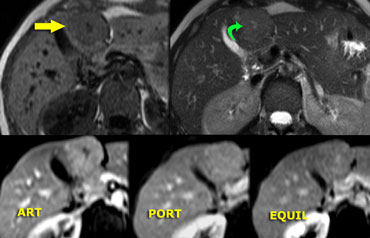

Small FNH Small FNH

Focal Nodular Hyperplasia (5)

On the left another FNH on MR.

The lesion is almost isointense to liver on T1WI and T2WI, but shows more contrast to the liver on a T1W-MPRGRE (gradient-echo).

The enhancement in the arterial phase is lobulated with nonenhancing septation and in the equilibrium phase the lesion is not different from normal liver parenchyma.

Notice that the lesion has a small scar.

Small FNHs often do not have a central scar on imaging and even not on pathologic examination.

Incidental hypervascular lesion on a CTA for pulmonary emboli Incidental hypervascular lesion on a CTA for pulmonary emboli

Focal Nodular Hyperplasia (6)

Another FNH on the left, in order to get really familiar with these common lesions.

On a CTA for pulmonary emboli a small hypervascular lesion is seen in the liver.

Further evaluation was done with MR.

On T1WI the lesion is not seen and on T2WI it is only slightly hyperintense.

In the arterial phase there is homogeneous enhancement and in the venous phase the lesion is not seen.

Provided that this patient does not have liver cirrhosis, this is probably a benign lesion, probably FNH.

As the appearance was not pathognomonic for FNH, a follow up examination was done and the lesion had not changed, making the diagnosis FNH most likely.